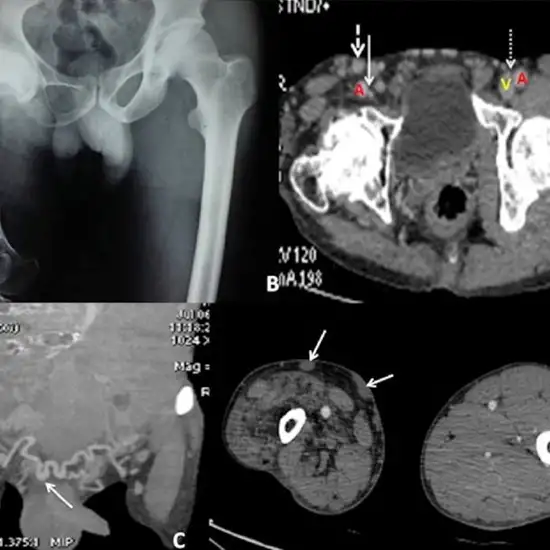

A CECT (Contrast-Enhanced Tomography) of the right hip joint is an imaging scan that uses an X-ray beam and contrast media to obtain cross-sectional images and provides doctors with detailed information about the right hip joint.

A CECT hip joint scan is a diagnostic imaging procedure that operates on the x-ray principle, the procedure involves the usage of a contrast media. After injecting the media, cross-sectional images of the concerned area are obtained that provide detailed information that helps in diagnosis and treatment plan.

Most commonly a CECT scan for the hip joint are done to assess the structures of the hip joint including the articular cartilage, the scan can be used to visualise and diagnose labral tears in cases where the MRI is contraindicated

The CECT scans for hip joints can show hip replacements. That aid in the diagnosis and treatment planning.